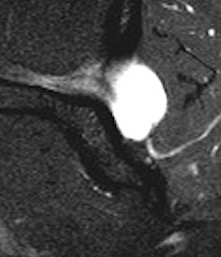

Spinoglenoid Cyst

Causes

Posterosuperior labral tears & SLAP tears

- labral tear acts as a one way valve

- repairing the labral tear is usually sufficient to solve the problem

MRI

Spinoglenoid cyst with SLAP tear and posterosuperior labral tear